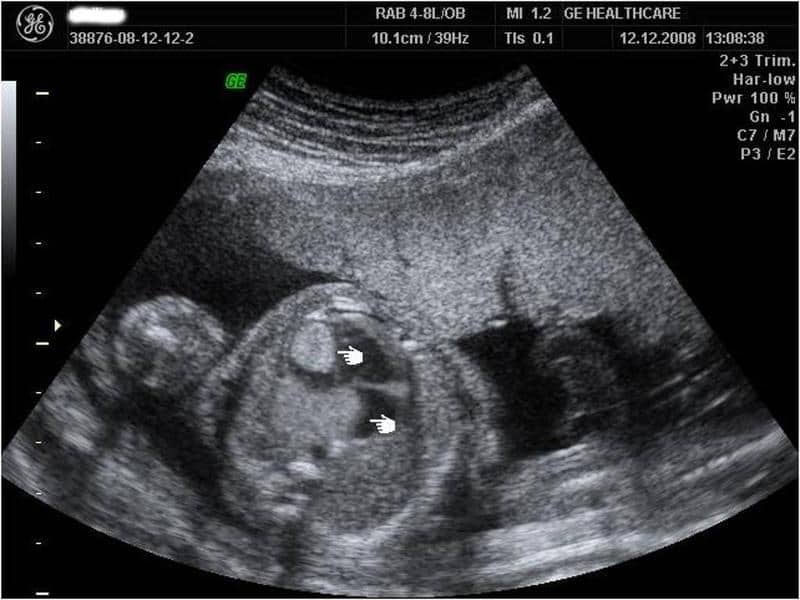

Rhabdomyoma:

- Paediatric chest x-ray showing cardiomegaly.

- The most common primary cardiac tumour in children.

- It is associated with the ventricular myocardium and appears homogeneously hyperintense on T2-weighted images.

- 50 to 70% are associated with tuberous sclerosis.

- Spontaneous regression is common.